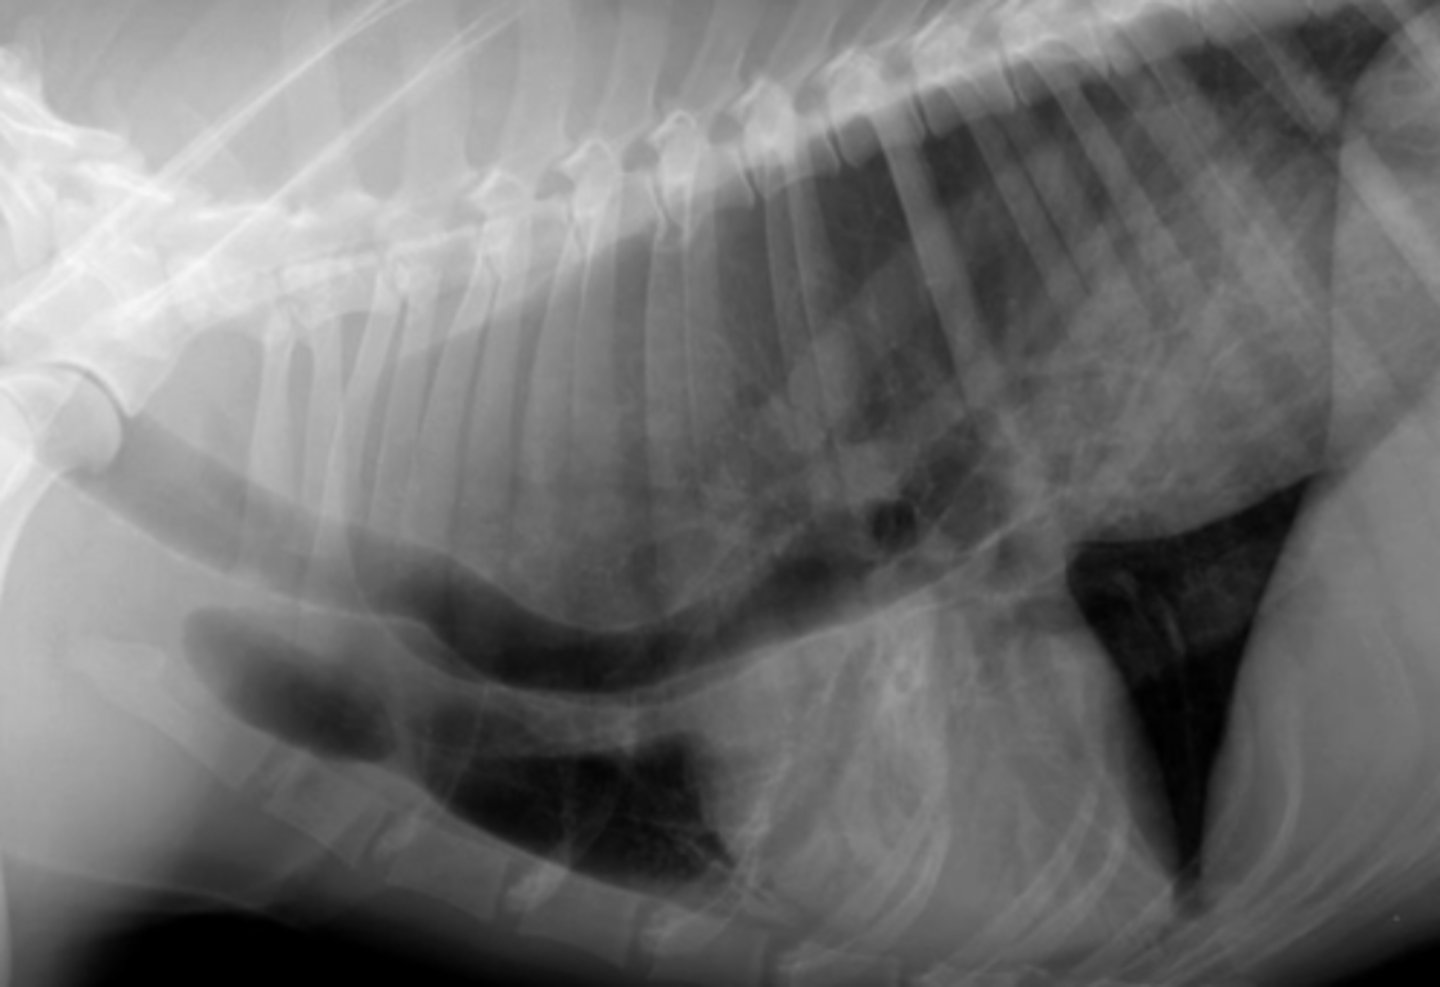

GDV

10 yo lab with abdominal distention, panting- what has caused this?